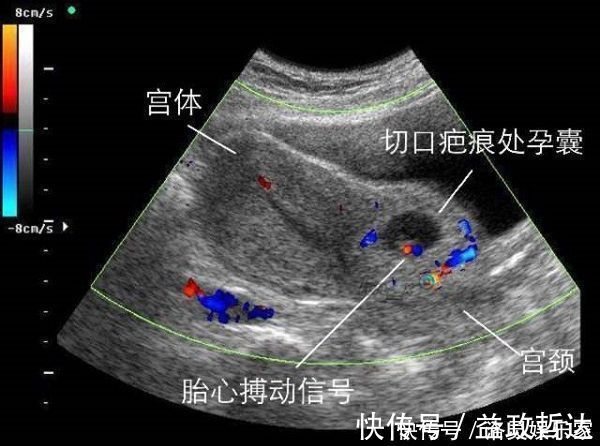

正当她为自己年轻的身体而窃喜时,却突然发现有一个小惊吓,原来以为身体有异样,检查之后发现自己怀孕了。因为头胎是剖腹产,医生嘱咐想要生二胎的话要在三年以后,但是这还没有半年就怀孕,那怎么行呢?当这个消息被家里人知道后,婆婆气定神闲地告诉她,村里还有人一年做了两次剖腹产,也没见人家有什么危险,医生说话都是吓人的。就这样,网友骆驼就把这个孩子留了下来。但是到了怀孕30周后的一天早上,突然肚子剧痛,当送到医院时,B超显示子宫已经破裂,孩子的脚丫子都伸了出来,腹腔里已经满是鲜血。经过急救,自己的命保住了,但是孩子却没保住,这时她才后悔没有听医生的话。

为什么医生让隔上两三年再生二胎呢?在怀二胎的时候,女性应该注意些什么呢?之所以在第一胎使用了剖腹产之后,要隔上两三年再怀老二,那是因为剖腹产让子宫上面受了伤,那条长长的伤疤虽然表面上看起来已经愈合,但是它里面的组织长得还不够结实。经过了两三年的修整,才能慢慢的恢复原来的弹性,如果像网友骆驼这样,在一年之内就想要在怀孕,在胎儿成长的过程中,伤疤会因为受不住剧烈的膨胀而崩开。